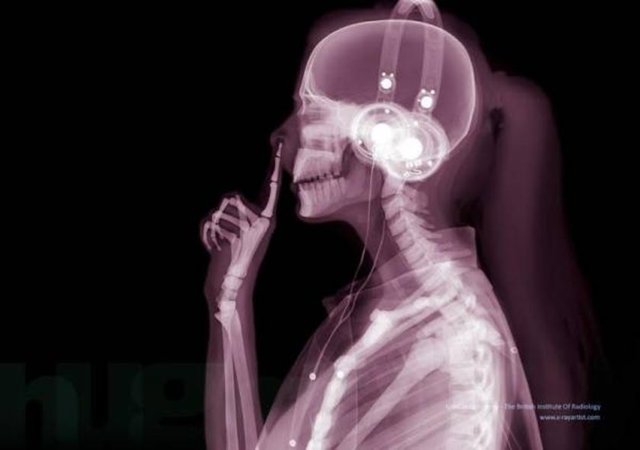

OMÜ Tıp Fakültesi Radyoloji Anabilim Dalı öğretim üyesi Prof. Dr. Çetin Çelenk, günümüzde bir çok yerde güvenlik amaçlı sıkça kullanılan metal kapı dedektörleri ile ilgili toplumda yanlış bir algı bulunduğunu dile getirdi. Sıklıkla iki tür güvenlik cihazının bulundurulduğunu bunlardan birinde X ışınının, diğerinde ise elektromanyetik alan kullanıldığını belirten Prof. Dr. Çelenk, şunları söyledi:

"Özellikle havaalanlarındaki girişlerde iki tür cihazı da görebiliriz. Eşyaların geçirildiği X-Ray cihazında X ışınları kullanılarak görüntüleme yapılır. Çantaların içinde ne olduğu X ışınları ile görüntülenir. Burada uygulanan X ışınlarının eşyalara bir zararı yoktur, birikmez, eşyalarda radyasyon kirliliği yapmaz. Bu cihazların çevresi X ışınlarının insanlara zarar vermemesi için kurşun paravanlarla kaplıdır."